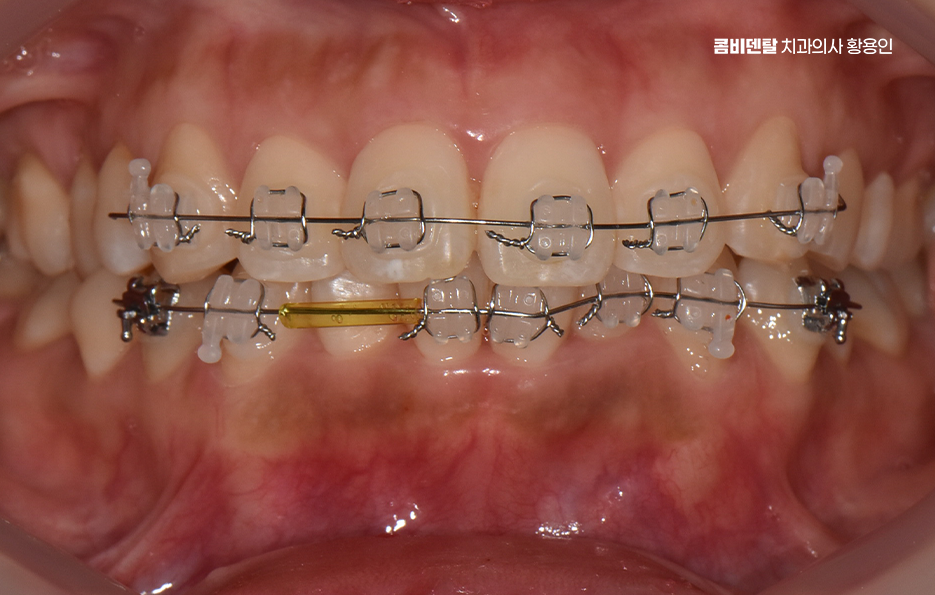

부분교정이 가능하다고 결론이 나면, 그때부터 어떤 방식으로, 얼마나 오랜 시간 동안 치료할 수 있을지 구체적인 계획을 세우게 되는 것이고 여기서 중요한 건, 부분 교정이라고 해서 모든 케이스가 간단하게 끝나는 건 아닌데 보통 3개월에서 6개월 정도면 끝난다고 하지만, 케이스에 따라 8개월 이상 걸리는 경우도 있고 유지 장치 착용도 고려하면 그저 단기 치료로만 끝나는 것은 아니기 때문에 치료 전에 교정 전문의와 충분히 먼저 상의가 필요한 거예요

전체적으로 보면 앞니 부분 교정은 치료에 대한 부담은 줄이면서 비교적 빠르게 앞니 치열을 개선할 수 있는 치료 방법이긴 하지만 조건이 맞아야 가능한 치료라는 점을 반드시 기억해야 하며 반드시 교정 전문의와 충분한 상담을 통해 진단을 받아야 하고 실제 교합 구조를 보면서 가능한 치료 범위와 한계를 분명히 이해한 후 치료를 결정해야 한다는 점에서 정확한 진단과 치료 목표 그리고 평생 결과를 유지하는 치아교정 결과라는 점에서 치과 선택부터 신중히 따져보시길 바라고 있어요